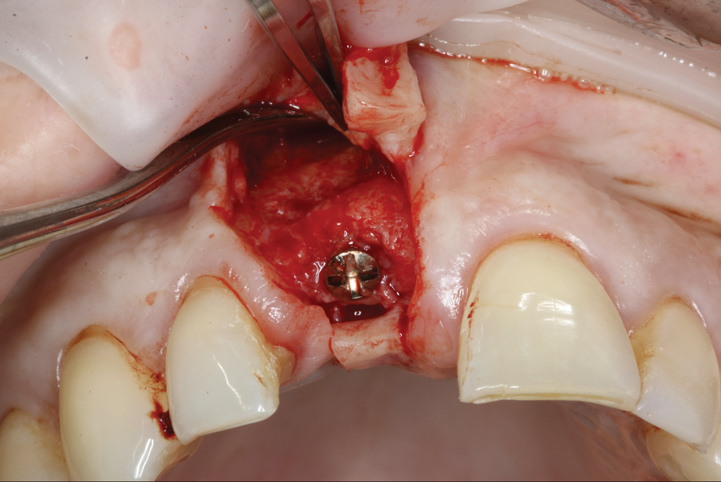

(17.) Implant placed 1-mm distal to the midline of the edentulous space, corresponding with the planned location of the gingival zenith. Note the lack of sufficient bone buccal to the implant that necessitated further grafting.

Figure 17

(21.) Postoperative periapical radiograph taken immediately after placement of the implant at site No. 8 demonstrating implant positioning centered with the planned location of the gingival zenith and two titanium alloy tacks that were used to stabilize the resorbable membrane apically.

Figure 21

Prior to the initiation of the surgery, the surgical guide was tried in to confirm proper seating and stability (Figure 15). A flapless approach was not considered because the need for further bone grafting at the time of implant placement had been anticipated through the digital planning. A slightly palatal crestal incision was made, followed by two vertical incisions on the mesial and distal aspects of the edentulous site in order to preserve the papilla and avoid additional esthetic compromise to the anterior sextant. Next, a full-thickness flap was elevated to facilitate removal of the tenting screw and permit visualization of the buccal plate (Figure 16). A standard guided protocol was followed to place the implant, and its final position mirrored that of the digital plan. As predicted, the prosthetically driven implant position resulted in an insufficient buccal plate (Figure 17); therefore, additional guided bone regeneration was performed to reinforce the area and prevent future breakdown (Figure 18 and Figure 19). Making periosteal incisions could have compromised the blood supply to the flap, so instead, it was stretched in order to achieve tension free coronal advancement.31The flap was secured utilizing horizontal mattress sutures with additional supportive interrupted sutures to ensure primary closure (Figure 20). An immediate postoperative periapical radiograph (Figure 21) and CBCT scan (Figure 22) were taken, demonstrating a final implant position centered with the planned location of the gingival zenith.

The digital wax up allowed the implant position to be planned based on the ideal prosthetic position of the final restoration (Figure 14). The planned implant position adhered to the aforementioned guidelines for ideal implant placement regarding the buccal, interproximal, and apical bone, and its platform would be located 4-mm apical to the planned restorative margin. In the coronal plane, the implant was centered with the gingival zenith in a position that was located approximately 1-mm distal to the midline of the edentulous space. Following implant planning, a tooth-supported surgical guide was designed and then 3D-printed to facilitate fully guided surgical implant placement.